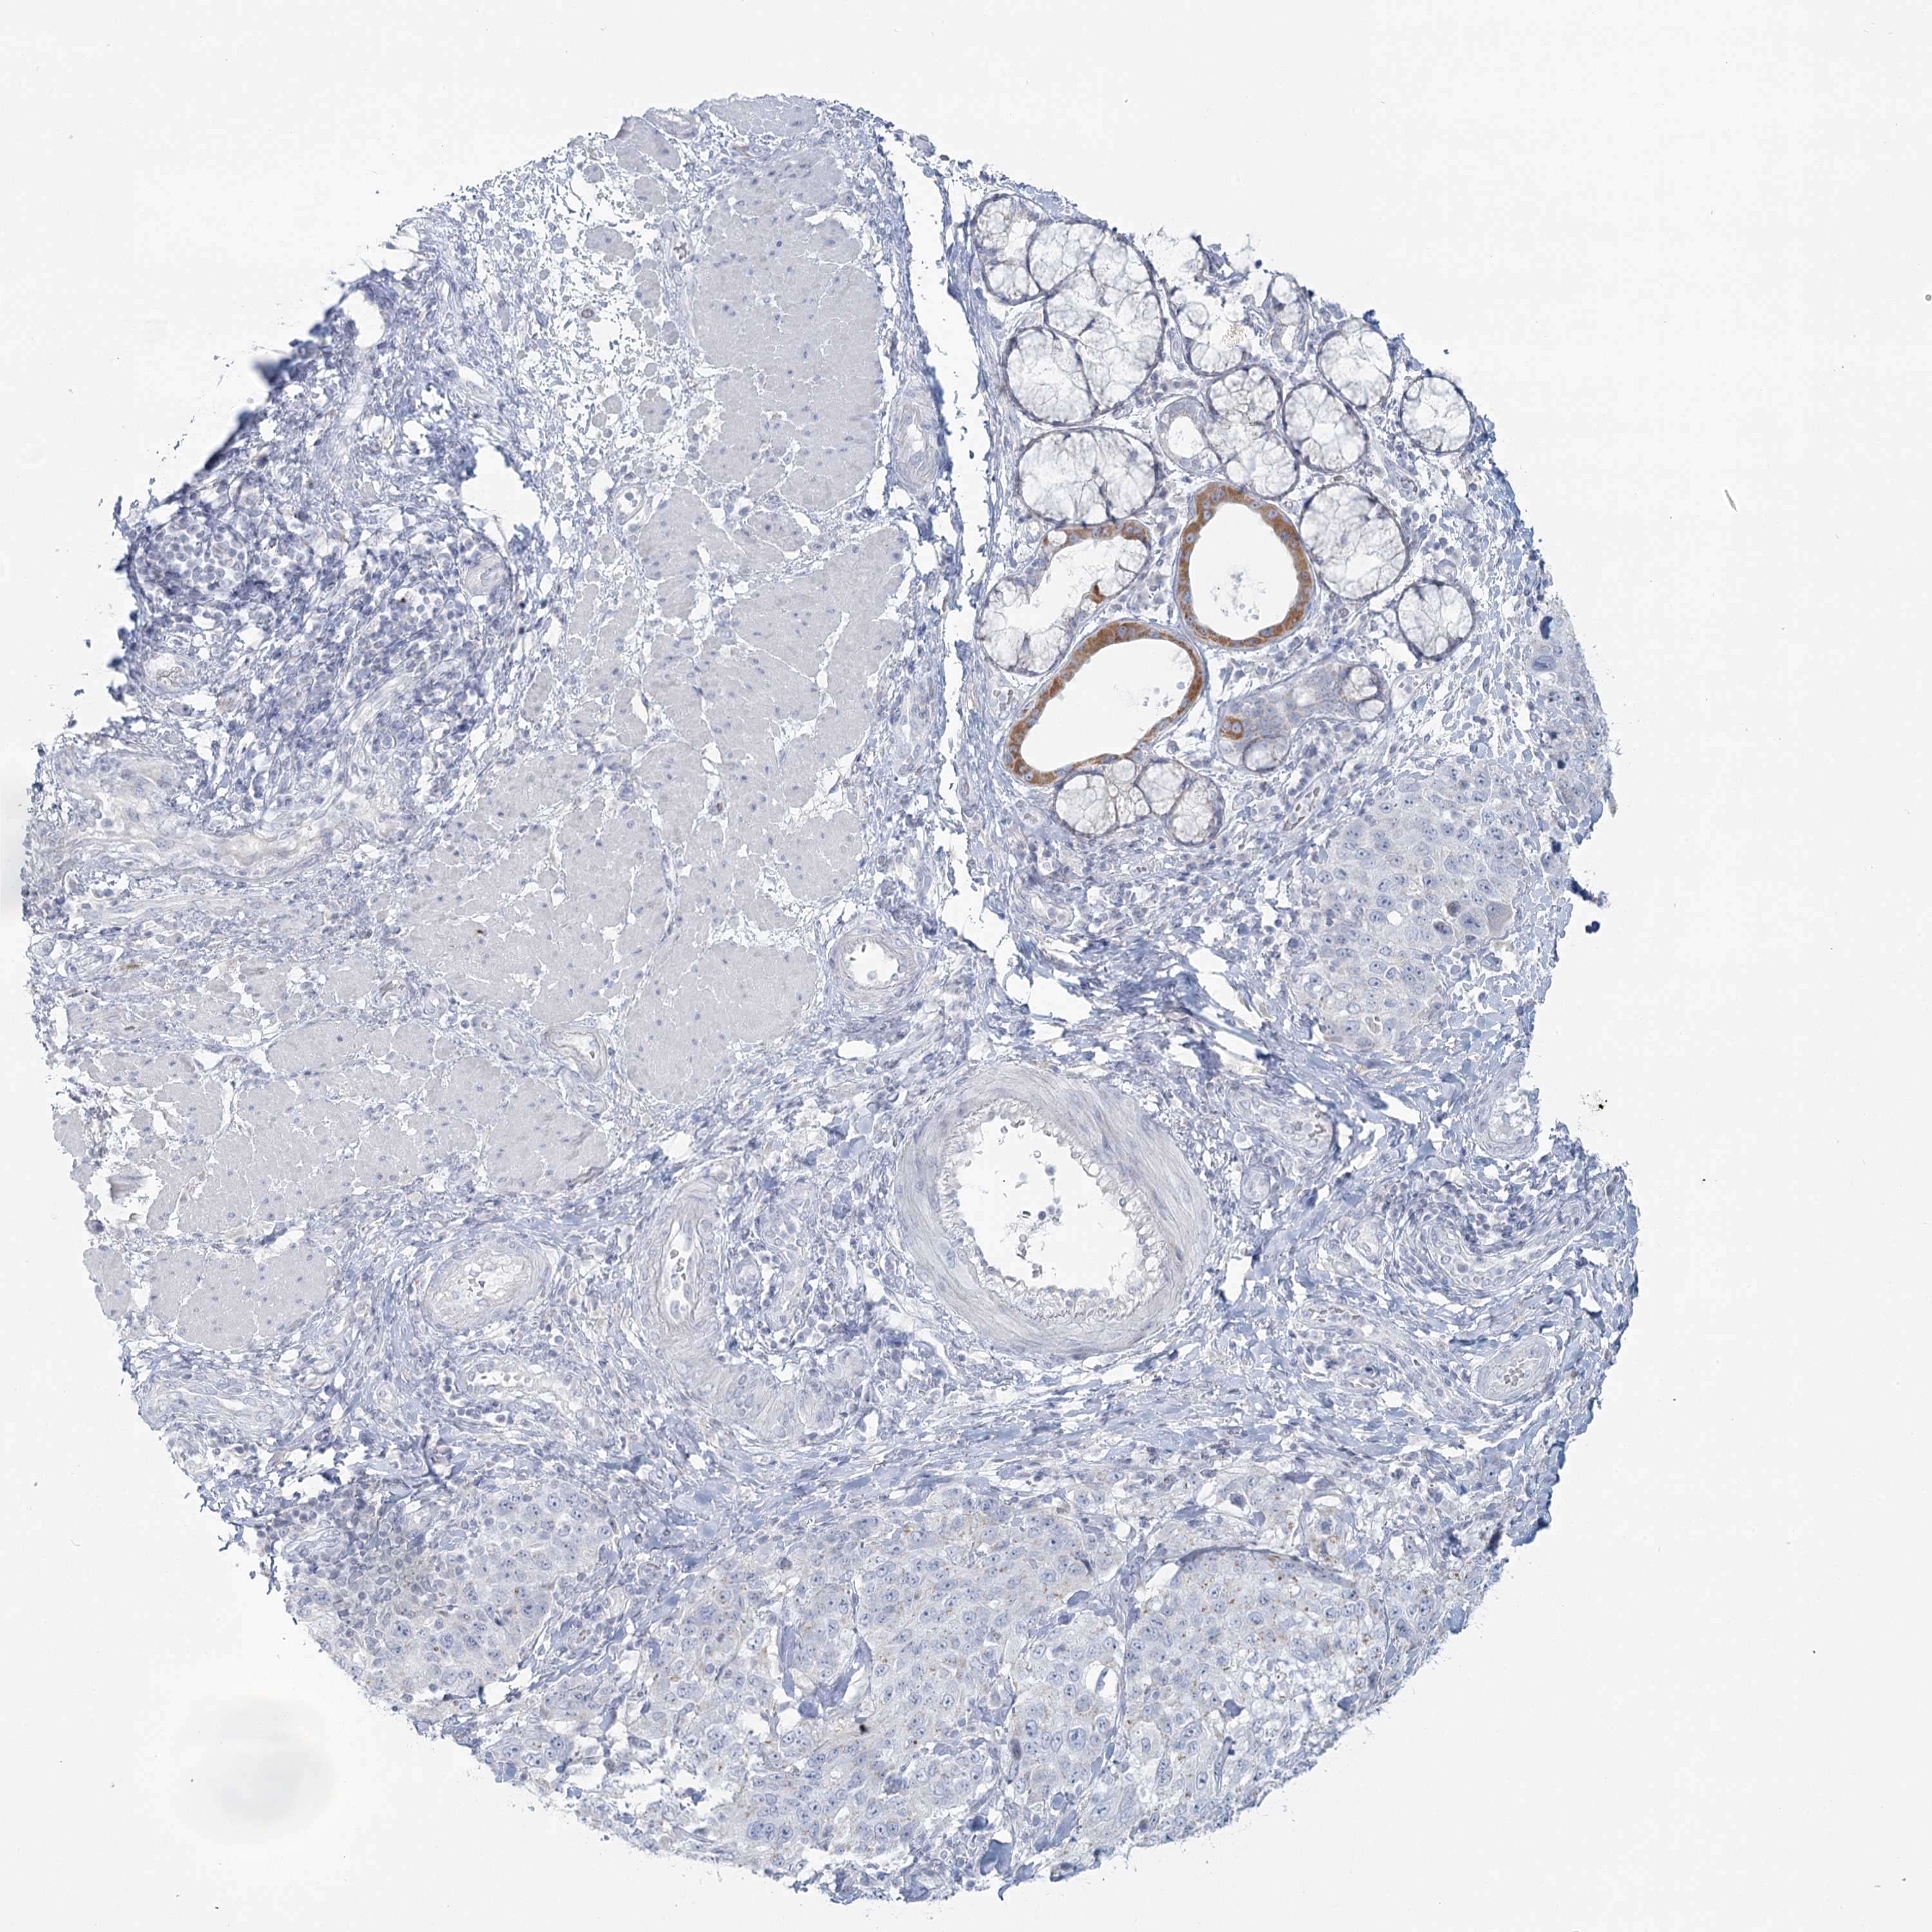

STOMACH CANCER - Protein expressioni

A mouse-over function shows sample information and annotation data. Click on an image to view it in a full screen mode. Samples can be filtered based on level of antibody staining by selecting one or several of the following categories: high, medium, low and not detected. The assay and annotation is described here.

Note that samples used for immunohistochemistry by the Human Protein Atlas do not correspond to samples in the TCGA dataset.

Antibody stainingi

Antibody staining in the annotated cell types in the current human tissue is reported as not detected, low, medium, or high, based on conventional immunohistochemistry profiling in selected tissues. This score is based on the combination of the staining intensity and fraction of stained cells.

Each image is clickable and will lead to virtual microscopy that enables deeper exploration of all samples and also displays staining intensity scores, fraction scores and subcellular localization as well as patient and tissue information for each sample.

Antibody HPA036752

Antibody HPA036753

Adenocarcinoma, NOS